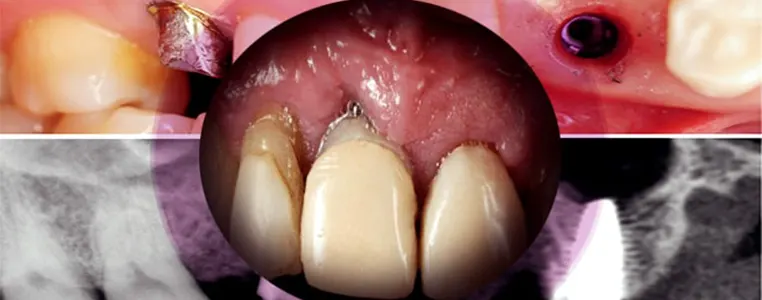

ایمپلنت دندان از سه بخش اصلی پایه ایمپلنت، آباتمنت و روکش ایمپلنت تشکیل شده است، پایه ایمپلنت اغلب از جنس فلز تیتانیوم است، این فلز سازگاری خوبی با بدن انسان دارد و می تواند بعد از مدتی با استخوان فک ادغام شده و جوش بخورد.

طبق مطالعات و تحقیقات گزارش شده در مجلات دندانپزشکی بین المللی، این عارضه با علایمی همراه می باشد، از جمله نشانه های رایج در رابطه با واکنش آلرژیک به ایمپلنت می توان به اریتم یا قرمزی بافت اطراف ایمپلنت، کهیر، اگزما، درد و التهابات محل ایمپلنت، نکروز، واکنش های سمی و توکسیک در سایر بافت های بدن مانند ریه ها و راه های هوایی، تحلیل و از بین رفتن استخوان اشاره کرد. توصیه می گردد نسبت به این علایم حساس باشید و در صورت بروز هر یک از این موارد به پزشک مراجعه نمایید.

در واقع حساسیت به ایمپلنت دندان ناشی از واکنش ایمنی افراد نسبت به فلز تیتانیوم می باشد که در پایه های ایمپلنت به کار می رود، طبق تحقیقات انجام شده فلز تیتانیوم (Ti) سازگاری بالایی با بدن داشته و از این رو در پروتزهای داخلی به کار می رود، با این وجود در برخی از افراد این راهکار با شکست مواجه می گردد.

فلز تیتانیوم در برابر خوردگی بسیار مقاوم است، در واقع تشکیل یک لایه سطحی اکسید غیر فعال سبب مقاومت بالای آن در برابر خوردگی می گردد، اما در صورت شکست در این لایه ممکن است شاهد عوارضی باشیم، آزاد شدن یون ها و در پی آن تشکیل کمپلکس با پروتئین های بدن سبب تشکیل آلرژن و بروز واکنش های حساسیت به ایمپلنت دندان می گردد.